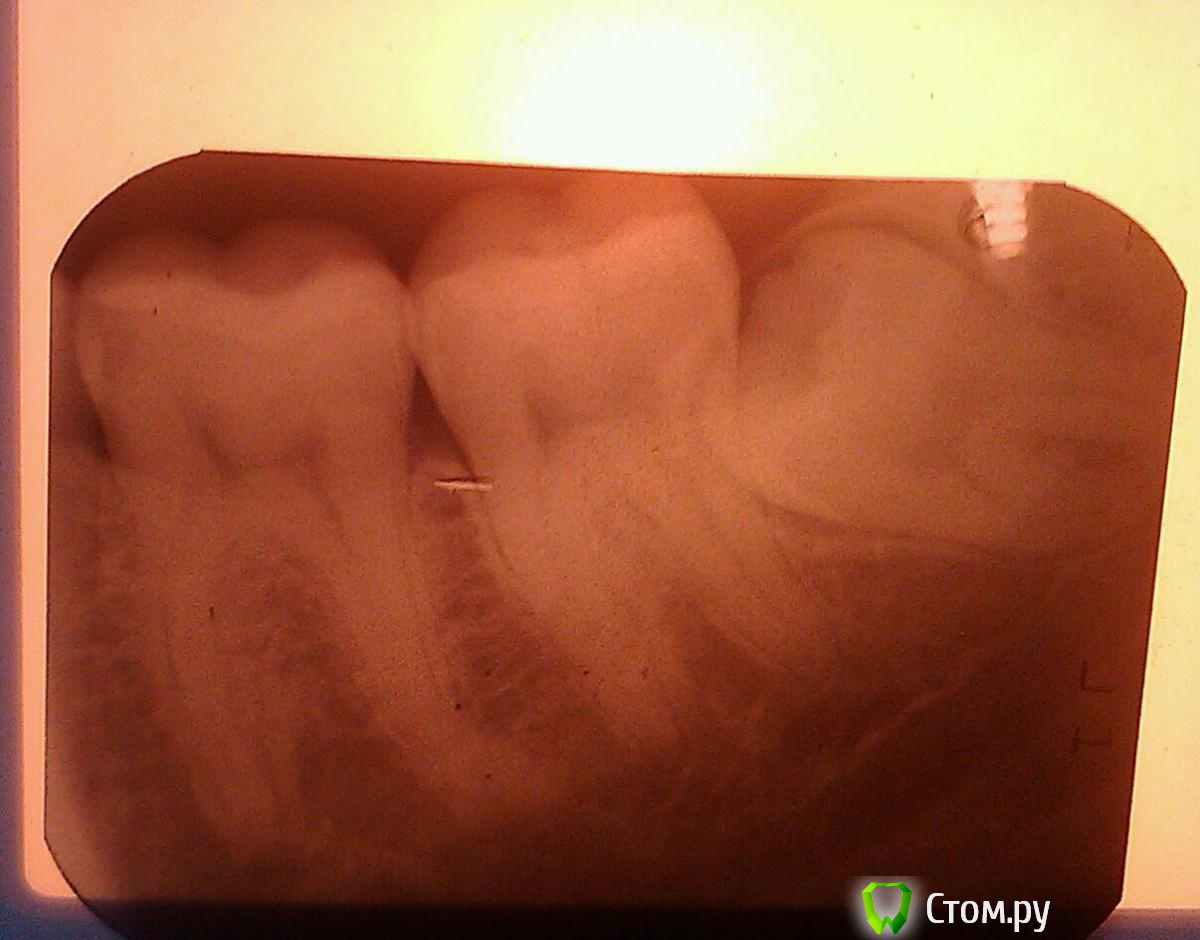

Аслан Опубликовано 23 октября, 2014 Поделиться Опубликовано 23 октября, 2014 Простите, но ни фига себе вы отслоились... По имеющемуся ужасному снимку глубина залегания средняя, удаление из разряда "работаем быстро и аккуратно", никаких анатомических сюрпризов.Остеотомия - это просто пилили кость? Зуб целиком вывихнули или делили на части? Ссылка на комментарий

Kostoprav Опубликовано 24 октября, 2014 Автор Поделиться Опубликовано 24 октября, 2014 (изменено) сори медиальная крыловидная (постоянно путаю) на снимке действительно кажется что зуб поверхностно лежит но на самом деле достаточно глубоко в кости корни развернуты в язычную стенку получается зуб как бы по диагонали лежал плюс своей коронкой корни семерки подпирал. я думаю что при остеотомии нерв и чиканул (фрезой когда язычную стенку пилил), а уверен я потому что другого анатомического образования между медиальной крыловидной мышцой и н\ч в этом сегменте нет, впрочем сегодня на повторном осмотре думаю мои опасения подтвердятся( Изменено 24 октября, 2014 пользователем Kostoprav Ссылка на комментарий